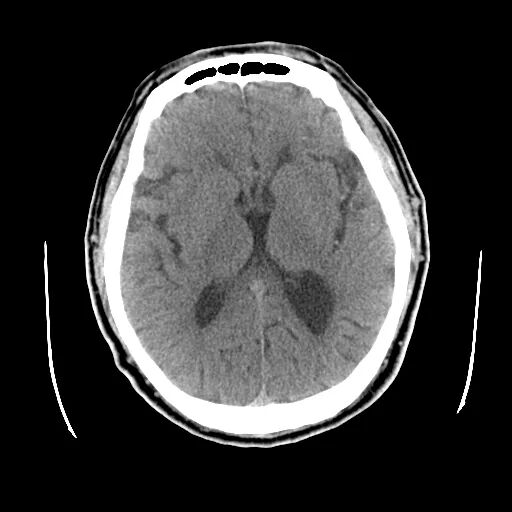

颅脑CT:颅内多发腔隙性梗塞灶。

什么叫桡鞘【例久弥新】寻道于桡——瑞康通5.5F Introsky X导管鞘经桡入路治疗颈动脉重度狭窄一例_https://www.jmylbn.com_新闻资讯_第2张